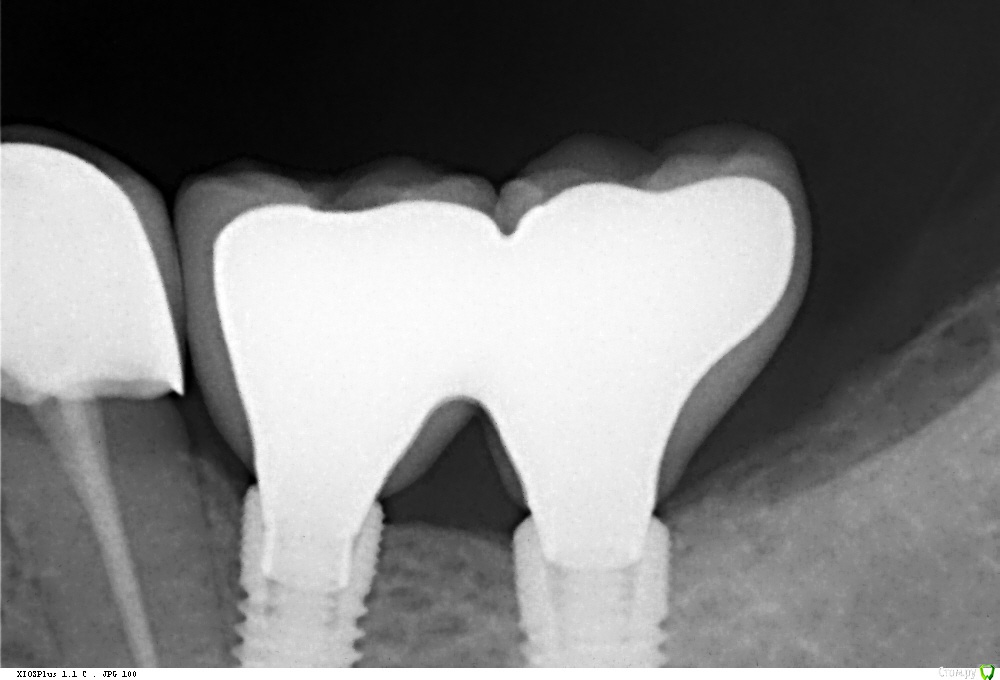

Павел7809 Опубликовано 3 декабря, 2016 Поделиться Опубликовано 3 декабря, 2016 Собственно зафиксировал коронки сегодня. Фиксация винтовая. Все село ароде как надо по прикус и эстетике супер.Но снимок меня смутил. Я прав? Ссылка на комментарий

zubovnet Опубликовано 3 декабря, 2016 Поделиться Опубликовано 3 декабря, 2016 Это Дентиум ? я так понял дистальный без шестигранника просто. Поэтому такая картина. Нет? Ссылка на комментарий

Павел7809 Опубликовано 3 декабря, 2016 Автор Поделиться Опубликовано 3 декабря, 2016 Точно! Вроде разобрался, надо было быть повнимательнее... Ссылка на комментарий